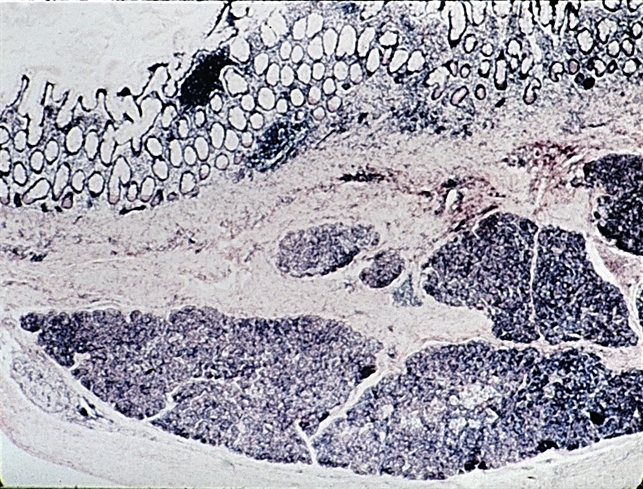

- teratoma, pancreatic tissue

- Teratoma under higher magnification shows pancreatic tissue in the wall of the intestine (H&E x20).